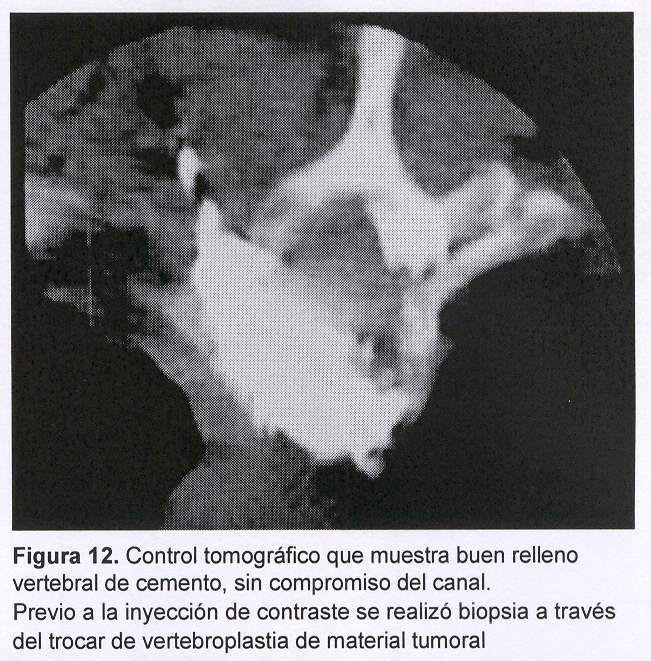

Se decide realizar vertebroplastia percutánea de T2 por vía lateral derecha con control tomográfico durante la introducción del trocar en el cuerpo vertebral (figuras 11 y 12). El objetivo fue, entonces, disminuir el dolor, estabilización verterbral y toma de muestras de tejido tumoral para anatomía patológica.